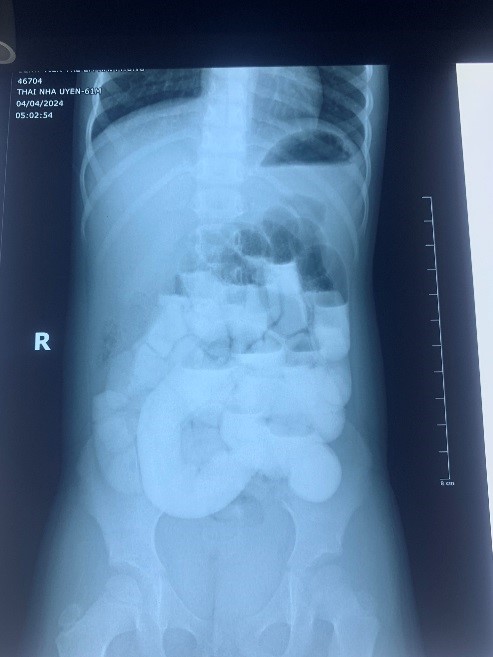

Hình 1(phim chụp lưu thông ruột): sau 8 giờ thuốc vẫn ở ruột non, không sang được ruột già

như chụp cắt lớp vi tính ( hình ảnh tắc ruột do dây chằng) , chụp lưu thông ruột